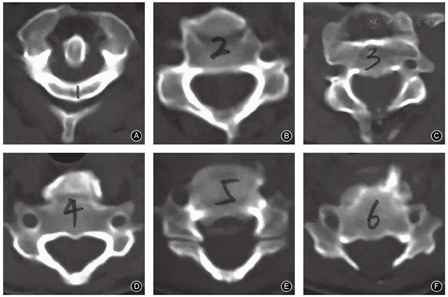

肺通气功能检查示肺通气功能及换气功能均正常。颈部血管CTA检查示双侧椎动脉走形及与周围组织毗邻关系基本正常(图2D)。颈椎CT及三维重建评估患者椎弓根发育情况,未见明显的椎弓根异常情况(图3)。CT示椎体无明显的楔形变,椎间隙中部高度C3,4为4.8 mm、C4,5为4.7 mm、C5,6为6.2 mm,C5椎体后方移位,C6,7椎间隙呈前宽后窄。